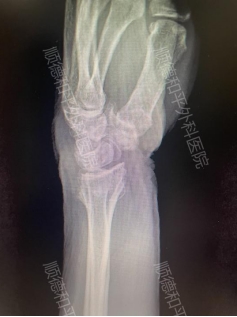

病例1:林女士(化名),74岁,左桡骨远端闭合性骨折+左尺骨茎突骨折

外院手法复位+石膏固定后仍疼痛难忍,家属寻求更优治疗。

治疗方案:关节镜辅助下桡骨远端骨折复位+可吸收螺钉+克氏针内固定术。手术仅1小时,创口微小,术后肿胀轻,疼痛显著减轻。患者快速康复,家属反馈:“终于不用看她天天忍痛了!”